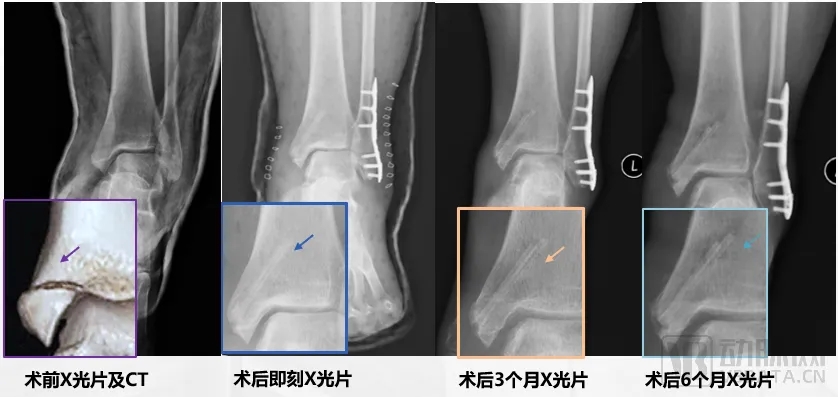

在临床试验的入组过程中,患者未出现任何产品相关的不良反应或并发症。对于已经使用镁合金接骨螺钉的受试者,在术后六个月的随访中,结果显示骨折愈合情况均达到优秀标准,填补了该领域空白。